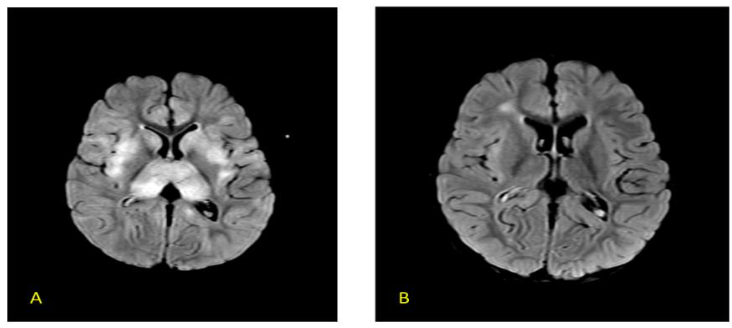

AFCE and AEM/HSES represent severe end of the spectrum of ITES, characterised by life threatening hyperacute onset of cerebral oedema or multi-organ dysfunction respectively. They carry a high mortality rate of about 80%. Both the entities have similar clinical presentations and radiological findings and probably are a part of the same severe neuro-inflammatory process.

AFCE and AEM/HSES represent severe end of the spectrum of ITES, characterised by life-threatening hyperacute onset of cerebral oedema or multi-organ dysfunction respectively. They carry a high mortality rate of about 80%. Both the entities have similar clinical presentations and radiological findings and probably are a part of the same severe neuro-inflammatory process.

FIG 8 (A–B) Axial CT scan in a 7-year-old with AFCE showing diffuse cerebral edema (A) with ‘white’ cerebellum sign (reversal) (B) – prognosis is very poor in this case (Image courtesy – Dr Nihal Reddy, Consultant Neuro-radiologist, Hyderabad)